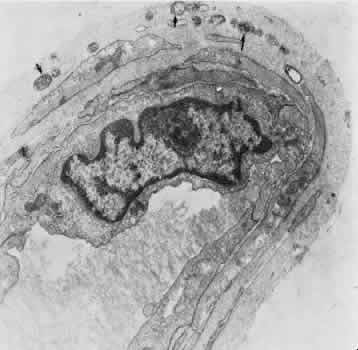

Retinal Veins and Venules Retinal veins are present in the inner retina, where they occasionally interdigitate with their associated arteries. When the two vessels cross, the artery usually lies anterior (toward the vitreous) to the vein.16 About one third of the time, however, the vein is anterior. At such crossing sites, the two vessels share a common adventitial coat.17 Under normal circumstances, the crossing vein's lumen may be decreased by as much as one third as a result of compression from the accompanying artery.17 There are many more arteriovenous crossings temporally than nasally, because the nasal vessels assume a much straighter course. Arteriovenous crossings are important because they represent the most common site of branch retinal vein obstructions. The separation of the superior and inferior halves of the perfusion of the retina is mirrored in the venous drainage pattern as well. Rarely does a retinal vein cross the horizontal raphe under normal circumstances. The retinal veins drain into the CRV, which also acts as the major efferent channel for the vessels of the optic nerve. Near the disc, the retinal veins are approximately 150 μm in diameter. Throughout the retina, the veins and venules generally follow the course of the arteries and arterioles. The intima of the veins consists of a layer of endothelial cells surrounded by a basement membrane continuous with that of the innermost layer of smooth muscle cells of the media. The media of the largest veins in the posterior retina consists of several layers of longitudinally oriented smooth muscle cells. The adventitia makes up the greatest part of the vessel wall and consists of loosely arranged collagen fibers and adventitial cells and is in direct contact with the glial cells of the retina. Venules are usually less than 20 μm in diameter.15 The media is composed of a single layer of cells resembling pericytes, containing poorly developed myofilaments and dense bodies. Elastin is not present. The adventitia contains little other than the basement membrane surrounding the pericyte (Fig. 5). Retinal Capillaries Throughout most of the posterior retina, the retinal capillaries are arranged anatomically in a dual layer. The superficial capillary layer is associated with the ganglion cell layer, whereas the deep capillary layer resides within the inner nuclear layer. Like capillary networks elsewhere in the body, the retinal capillaries assume a meshwork configuration to ensure adequate perfusion to all retinal cells. The deeper layer has a mesh diameter (i.e., the distance betweencapillaries) that characteristically averages 50 μm in diameter but varies between 15 and 130 μm. The more superficial layer has a slightly larger meshwork, on average 65 μm in diameter (16 to 150 μm). In the midequatorial and anterior zones, where the retina is thinner, only one capillary layer is present. In the fovea and the far retinal periphery, retinal capillaries are absent. The precise anatomical localization of the superficial layer of retinal capillaries appears to depend on the thickness of the accompanying ganglion cell layer.18 In the foveola itself and in the immediate parafoveal retina that contains a ganglion cell layer less than 15 μm thick, there are no superficial capillaries. This area represents the foveal avascular zone. Pathologic conditions that feature retinal capillary dropout, such as diabetes mellitus and sickle cell disease, may show an enlargement of this foveal avascular zone. Near the foveal margin, where the ganglion cell layer is of moderate thickness, the superficial retinal capillaries can be found in the outer aspect of the ganglion cell layer. In the intermediate parafoveal area, which has a ganglion cell region thicker than 45 μm, the superficial retinal capillaries are present within the ganglion cell layer itself. In the perifoveal region, where the ganglion cell layer is two to four cells thick, the superficial capillaries are found along the inner boundary of the ganglion cell layer, in contact with the nerve fiber layer. The major retinal vessels, especially the larger ones, usually are in contact with both the inner and outer boundaries of the ganglion cell layer. A capillary-free zone is present around each of the larger retinal arteries and veins (Fig. 6). It is more prominent around the arteries, measuring up to 100 μm. The capillary-free zone is a product of the embryologic vascular remodeling process. Direct diffusion of oxygen through the walls of the large retinal vessels probably initiates this process of vascular remodeling. Embryologically, numerous capillary-sized channels retract from the developing artery, leaving only a relatively few right-angled side-arm channels to serve as precapillary arterioles. In keeping these side channels to a minimum, the maintenance of an adequate pressure head for the remainder of the retina is ensured. In contrast, the radial peripapillary capillaries (RPCs) may develop in a different fashion, later than the other capillary beds, after vascular remodeling has already occurred.19 A distinct layer of capillaries, the RPC, is found adjacent to the optic disc, most prominently in the superior and inferior temporal aspects of the posterior pole (Fig. 7).20 These capillaries originate only from intraretinal arterioles and not from the optic disc vasculature. They are found within the inner aspect of the nerve fiber layer, making them the most superficial of all retinal capillaries. The RPCs tend to follow relatively long, straight paths, having few anastomoses with adjacent or underlying capillary beds. The RPCs do not traverse the central macular area. Their distribution suggests some anatomical correlation with various diseases. Cotton-wool spots are found in a distribution similar to the RPCs, and the arcuate scotoma seen in glaucoma appears to correspond to their pattern as well.21 The superficial peripapillary hemorrhages seen in glaucoma (Drance hemorrhages) may originate with the RPCs as well.22 Retinal capillaries range in diameter from 4 to6 μm. The capillaries throughout the retina, including those of the radial peripapillary network, have the same fine structure.23 The capillary wall consists of a continuous layer of flattened and longitudinally oriented endothelial cells and an incomplete layer of longitudinally oriented pericytes (Fig. 8). The pericytes (formerly referred to as mural cells) are closely spaced, resulting in an approximate ratio of pericytes to endothelial cells of 1:1, a relatively high ratio compared with elsewhere in the central nervous system. Ultrastructural examination of the endothelial cells of retinal capillaries shows that the cytoplasm of the cell bulges in the region of the nucleus. This area contains the Golgi apparatus, centrioles, and rough-surfaced endoplasmic reticulum. The remainder of the cytoplasm contains moderate amounts of smooth endoplasmic reticulum and mitochondria. The average endothelial cell thickness is 236 nm. Pinocytotic vesicles occur in the cells of the retinal capillaries. The vesicles are of uniform size, with an average diameter of 70 nm. Pinocytotic vesicles are found on the lumen (10% of total) and basement membrane (28%) side of the endothelial cells and free in the cytoplasm (62%). Approximately 2% of the volume of the endothelial cell is occupied by pinocytotic vesicles, a number that is substantially lower than that of other continuous capillaries. Pinocytotic vesicles of similar morphology and location are found in pericytes, but not in any number on glial cell membranes. Animal experimental evidence shows that these vesicles may be responsible for transporting substances from the vitreous cavity into the retinal vasculature in a unidirectional fashion.24 In the region of the endothelial cell junctions, cytoplasmic processes may overlap and form flap-like extensions that project into the lumen. The outer leaflets of adjacent endothelial membranes form very tight occluding junctions. The basement membrane surrounding the endothelial cell is well developed and continuous with the basement membrane surrounding the pericytes. The basement membrane of the retinal capillaries is structurally similar to that of the retinal arteries and veins in that collagen types 4 and 5, laminin, and heparin sulfate proteoglycan core protein are prominent features. Collagen types 1 and 2 appear to be lacking.12 Some areas show thinning of the basement membrane, and in these regions the endothelial cells and pericytes are closely apposed. Specifically, the capillary basement membrane between pericytes and endothelial cells is much thinner than the basement membrane covering the two types of cells.25 This arrangement probably allows increased communications between the cells. The retinal capillary basement membrane is thicker than in most other capillaries in the body, and in certain disease states such as diabetes, this thickness increases further.26 The pericytes of the retinal capillaries are not as elongated as the endothelial cells. They are endowed with multiple arm-like processes that wrap around the surrounding endothelial cells. Pericyte processes appear to cover about 85% of the entire circumference of the available capillary endothelial tube.25 Pinocytotic vesicles can be seen near the adventitial (outer) side of the cell body. In the peripheral retina, the retinal glial cells are in direct contact with the basement membrane surrounding the pericytes. Evidence suggests that the retinal pericytes are directly involved in the local control of retinal blood flow (RBF) and may affect endothelial proliferation as well.25 In diabetes there is an early, preferential loss of pericytes.27 Aldose reductase has been shown in the human pericyte, inviting speculation that abnormal accumulation of byproducts of this enzyme, such as polyol, may have a role in the selective pericyte loss.28 With aging there occurs a gradual loss of endothelial cells, followed by degeneration of the pericytes, an increase in capillary diameter, and a thickening and vacuolization of the capillary basement membrane surrounding the external surface of the pericyte.26,29 Age-related studies of larger retinal vessels show narrowing of the retinal arteries. This appears to be due to the fibrous replacement of contractile elements.17,30 These morphologic findings may account for the decrease in reactivity of the retinal arteries and arterioles to blood pressure and oxygen tension changes with age. A similar decrease in myogenic tone of the PCAs with age has also been demonstrated.31 OPTIC NERVE Most of the blood supply to the intraorbital portion of the optic nerve is through numerous perforating vessels from the pia mater. These pial vessels obtain their supply either directly from the ophthalmic artery or indirectly from recurrent branches back from the PCAs. There does not appear to be a “central artery of the optic nerve,” as once postulated.32,33 Axial branches off the CRA contribute to the circulation as well. The vascular supply of the optic nerve head was the source of considerable controversy in the past. The optic nerve head is situated at the watershed area between three separate circulations: the retinal, the posterior ciliary, and the pial (Fig. 9). Each of these systems contributes in part to the optic nerve head circulation. In some people, an incomplete arterial ring is formed within the sclera by the anastomoses of these three circulations. When present, it is referred to as the circle of Zinn-Haller. Most of the prelaminar blood flow is derived from the posterior ciliary circulation by way of the short PCAs.34,35 The prelaminar optic nerve may have separate tributaries from the short PCAs, or branches of these vessels may supply the optic nerve directly, as well as the choroid.36 There do not appear to be any direct anastomoses between the choriocapillaris and the capillaries of the optic nerve head, however. Neither are there major contributions from axial branches of the CRA. The circle of Zinn-Haller may contribute to the prelaminar circulation, but the pial arteries do not directly supply the prelaminar portion. They may anastomose with the prelaminar capillary network, however. The laminar portion of the optic nerve head is also supplied by the short PCAs, with variable contributions from the circle of Zinn-Haller.37 The CRA does not appear to contribute much to the supply of this area (Figs. 9 and 10).

In the retrolaminar zone, the contribution of the choroidal vessels is less. The peripheral aspects of the postlaminar optic nerve are supplied by the pial vessels, whereas the central portion is fed by the axial vessels off the CRA. The afferent channels derived from the short PCAs that cross the border tissue of Elschnig at the level of the choroid have a diameter ranging from 10 to 17 μm.36,37 They quickly branch into a tridimensional vascular network with a polygonal capillary bed. The capillary bed is nonfenestrated, with tight junctions. Numerous pericytes surround the endothelial cells. The capillary mesh measures from30 × 50 μm to 50 × 80 μm, and there are multiple arterial feeding points into the meshwork. The density of the meshwork seems equal in all disc quadrants. Although the capillary bed of the optic nerve head is derived mostly from posterior ciliary vessels, it more closely resembles the retinal capillary bed morphologically than the choriocapillaris. The major efferent vessel for this area of the optic nerve is the CRV. Some of the prelaminar drainage may be through the choroid as well. Direct communications between the CRV and choroidal veins may exist as a result of CRV obstruction or as anatomical variants, which would make the eventual drainage system the vortex veins. The surface capillaries of the optic disc are derived from the retinal vessels.35,37 They anastomose with capillaries of the retina. The prelaminar, choroidal-derived vessels may contribute somewhat to the surface capillary supply. The postcapillary venules that drain the RPC system cross over the disc margin to join with larger venules of the CRV system. It may be these terminal endings of the RPC that bleed with papilledema and other causes of disc swelling. The blood flow to the optic nerve head appears to be under local autoregulatory control.38–40 This flow pattern is similar to the retinal circulation. The site of the autoregulation is not clear; however, both endothelial cells and pericytes probably have a role. The clinical appearance of optic nerve blood vessels in various pathologic conditions has been the focus of intense interest. Alterations in optic nerve blood vessels associated with advancing glaucoma have been an area of particular study in light of the theories concerning a vascular origin for the disease. Quigley and colleagues41 noted that the density of optic nerve head capillaries did not appear to change with worsening glaucoma and that eventual loss of capillaries was in proportion to the accompanying loss of neural tissue. Jonas and associates42 showed that the diameter of parapapillary retinal blood vessels was smaller in eyes with advanced glaucoma than in eyes without glaucomatous damage. This finding appears to represent an autoregulatory response of the retinal and optic disc vasculature to the local loss of retinal ganglion cells and nerve fiber layer. This study confirms an earlier report showing a significant decrease of RBF to the retina in eyes that had undergone inner retinal degeneration.43 CHOROID The choroid is by far the most vascular portion of the eye and by weight is one of the most vascular tissues in the body.44 More than 80% of all ocular blood flow goes to the choroid. The choroidal circulation is responsible for the nourishment of the photoreceptor/retinal pigment epithelium (RPE) complex. Despite these facts, the choroidal circulation has received relatively little attention for two reasons. First, it is difficult to visualize the choroidal vessels directly, and second, there are relatively few pathologic conditions that have unequivocally been associated with a primary deficiency in choroidal circulation. Choroidal blood flow can be assessed in a qualitative manner with fluorescein angiography. The rapidity of choroidal filling, the normal permeability of the choriocapillaris, and the normal blockage of fluorescence as a result of the RPE impede the identification of choroidal perfusion defects. When present, the clinical significance of choroidal perfusion defects on fluorescein angiography is not always clear, either. Newer methods used to study choroidal perfusion more quantitatively include indocyanine green angiography and color Doppler ultrasonography.45,46 Indocyanine green angiography in particular has made the choroid more accessible to clinical evaluation and interpreting the role of the choroid in various disease entities. Along with its paramount task of providing nutrition to the outer retina and RPE, the choroidal circulation also has other roles. It serves as a heat sink, removing the large amount of heat that develops as a result of the metabolic processes initiated when photons strike the photopigments and RPE.47 In addition, the choroid itself probably serves as a mechanical cushion for the internal structures of the eye. The overall structure of the choroidal circulation is segmental.47–52 This segmental distribution of blood begins at the level of the posterior ciliary branches and is mirrored in the vortex vein drainage system. Because of the segmental distribution, the large and medium-sized choroidal arteries act as end arteries. Unlike most other tissues, in the choroid the large vessels do not run parallel to each other. The segmental distribution of blood flow to the choriocapillaris is reflected in certain disease states, such as malignant hypertension. Each terminal choroidal artery supplies an independent lobule of choroidal capillaries (Figs. 11 and 12). Examination of the lobular structure reveals that feeding arterioles are usually found in the lobule center with draining venules located at the lobular periphery, but reversals of this pattern are frequently seen. There is little or no functional communication between adjacent capillary lobules.53–56 The vasculature of the choroid appears to be under direct adrenergic innervation.13,57 It is hypothesized that the parasympathetic innervation is through the seventh cranial nerve by way of the pterygopalatine ganglion.58 Arteries and Arterioles Within the choroid, the arteries and arterioles lie in stratified layers, with the larger vessels located in the outermost layer. The innermost layer of choroidal vessels is a single layer of capillaries. The arteries of the choroid measure between 20 and 90 μm in diameter.59 The larger vessels contain an endothelium and basement membrane, an internal elastic membrane, and a single continuous layer of smooth muscle cells. The muscle cells contain abundant myofilaments, and pinocytotic vesicles are arranged along the inner surface of the plasma membrane. The adventitia is composed of bundles of collagen fibers, scattered elastic fibers, and occasional fibroblasts. In the smaller vessels (arterioles), the internal elastic membrane disappears, and the muscle layer becomes discontinuous and more circumferentially arranged. The collagen present in the adventitia also becomes considerably diminished. Veins and Venules The choroidal veins that directly feed the vortex veins have a diameter less than 150 μm.59 The veins with a diameter between 50 and 150 μm have an endothelium and basement membrane with one or two layers of smooth muscle and a relatively thick collagenous adventitia. In the venules (smaller than 40 μm), the intima is the same, but the media contains a discontinuous layer of longitudinally arranged pericytes. Choriocapillaris The choriocapillaris is the unique capillary system of the choroid. The vessels of the choriocapillaris are unusual because of their large diameters. The lumina are typically larger than 8 μm. Lumina of this size allow passage of multiple red blood cells at any moment in time. The choriocapillaris is arranged in a specific lobular pattern to ensure maximum exposure of the overlying outer retina/RPE complex. Each lobule acts as an independent vascular system with its own afferent and efferent vessels.60 Within the posterior pole region, there are more venules than arterioles, probably to allow rapid flow. Other local variations exist. The lobules at the posterior pole are 200 to 400 μm in diameter and gradually enlarge to 1,500 μm in the periphery and somewhat lose their lobular pattern (Fig. 13).54,61 The vessel walls themselves consist of fenestrated endothelium surrounded by a basement membrane and a sparsely arranged layer of pericytes. The portion of the endothelial cell containing the nucleus also contains most of the cell's cytoplasm and organelles. The remainder of the cytoplasm is extremely attenuated, and these regions contain the fenestrae. These fenestrae are approximately 700 to 800 nm in diameter and are covered by a diaphragm. The attenuated areas are most typically found facing the RPE and contain very few pinocytotic vesicles. The region of the cell facing the suprachoroidal space usually contains more cytoplasm, fewer fenestrae, and the nucleus (Fig. 14). Few pericytic processes are seen in cross sections of these vessels on the side of the vessel facing the pigmented epithelium (Fig. 15). However, these processes are more numerous on the surface of the vessel facing the sclera. Because of the fenestrae, the choriocapillaris actively leaks fluorescein molecules.